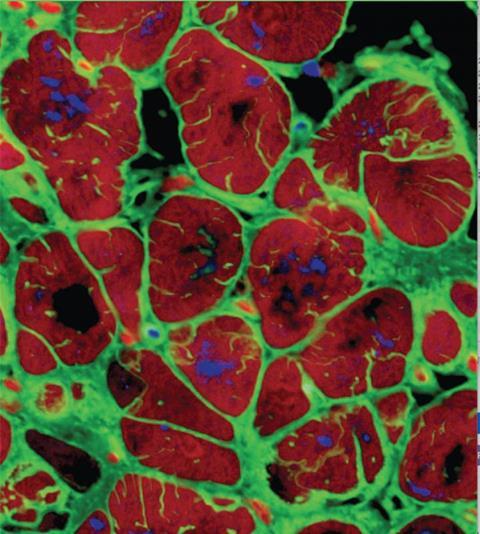

iPSC-CMs

iPSC-CMs provide an innovative platform to model cardiovascular diseases, enabling researchers to investigate toxicity and potentially produce personalised regenerative therapies that are more relevant to human physiology and reflect the genome of the subject. As well as this, the derivation of these cells is minimally invasive, and in theory could provide an unlimited supply of human cardiomyocytes.